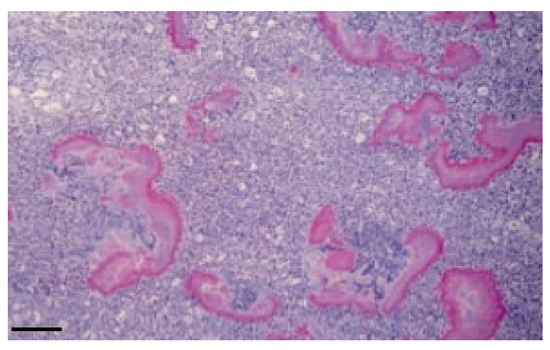

Histological examination revealed a loose connective tissue with scattered foci of granulomatosis. The granuloma is characterized by a mass of small aggregates of bacteria surrounded by numerous neutrophils, macrophages, plasma cells and some giant cells and by a wall of granulation tissue which developed into a connective tissue. The tissue was surrounded by eosinophilic club-like bodies. In addition to the granulomatous reaction, the Splendore–Hoeppli phenomenon was observed, characterized by hyaline, acidophil (Figure 3), and PAS-positive material (Figure 4) which is arranged as a crown of clavate protrusions around each colony. Gram stain was then carried out and results were Gram-negative bacteria.

Figure 3. Typical histological features of granulomatous disease due to A. lignieresii. (brain; HE). Bar: 20 μm.